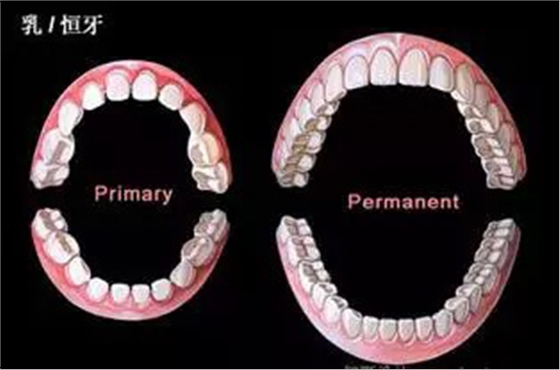

錯合畸形高發(fā)時間:

乳牙列和恒牙列早期

QQ圖片20150711104419.png

瑞典一項縱向觀察研究顯示,處于乳牙列和恒牙列早期的兒童錯合畸形的發(fā)病率高,亟需正畸治療;在乳牙列向早期恒牙列轉(zhuǎn)換的過程中,存在大量自我矯正和新的錯合畸形的發(fā)生。該論文于2015年4月13日在線發(fā)表于《安格爾正畸醫(yī)師》(Angle Orthod)雜志。

研究人員對277名納入兒童分別在其3歲、7歲和11.5歲進行隨訪,通過臨床檢查確定其是否患有錯合畸形和需要正畸治療,通過問卷調(diào)查和口腔檢查搜集患兒允指習(xí)慣、呼吸紊亂、過敏、口腔頜面外傷以及正畸治療的情況。

結(jié)果為,3歲兒童的錯合畸形發(fā)病率為71%,7歲時為56%,11.5歲時為71%;前牙開合、矢狀面方向的錯合、后牙反合可在一定程度上出現(xiàn)自我矯正,但深覆合會繼續(xù)加重;大量咬合接觸點的變化和牙間隙的出現(xiàn),導(dǎo)致11.5歲時錯合發(fā)病率高達71%;22%的患者亟需正畸治療;患兒3歲時的口腔不良習(xí)慣、過敏以及呼吸紊亂與其11.5歲時的錯合畸形并無明顯關(guān)聯(lián)。(陸慧 編譯)